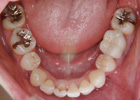

歯を抜いて治療した例 その1

治療前

治療途中

治療後